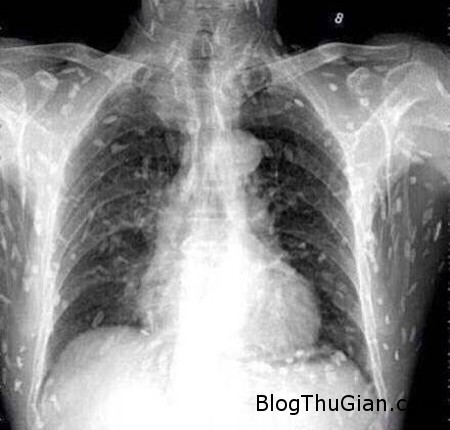

Tuy nhiên, do bệnh tình đã bước sang giai đoạn nghiêm trọng nên người đàn ông tiếp tục được chuyển tới Bệnh viện Nhân dân số 8 ở Quảng Châu để điều trị. Kết quả chụp X-quang cho thấy, những đốm trắng nhỏ xuất hiện lấm chấm khắp cơ thể chính là sán.

Những chấm trắng xuất hiện trên hình chụp X-quang là sán.